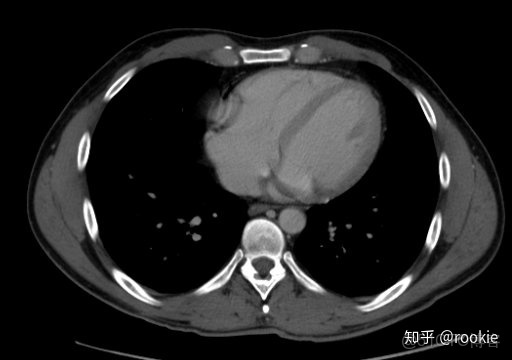

CTA窗口窗口設置: (W:600,L:170)或(W:650,L:225)優點: 在評估CT血管造影研究(或在血管中具有明顯對比的CT掃描的任何階段)時,此設置可用於嘗試清晰地觀察血管病變。它在提供目標血管信號的同時具有良好的平衡,而無需血管內的亮度過高會沖洗腔內病變。

CLAHE算法增強局部對比度的X光圖像增強效果對比_ico_14

此窗口用於在感興趣的血管中有相當大的對比度的情況下(例如CT血管造影)。